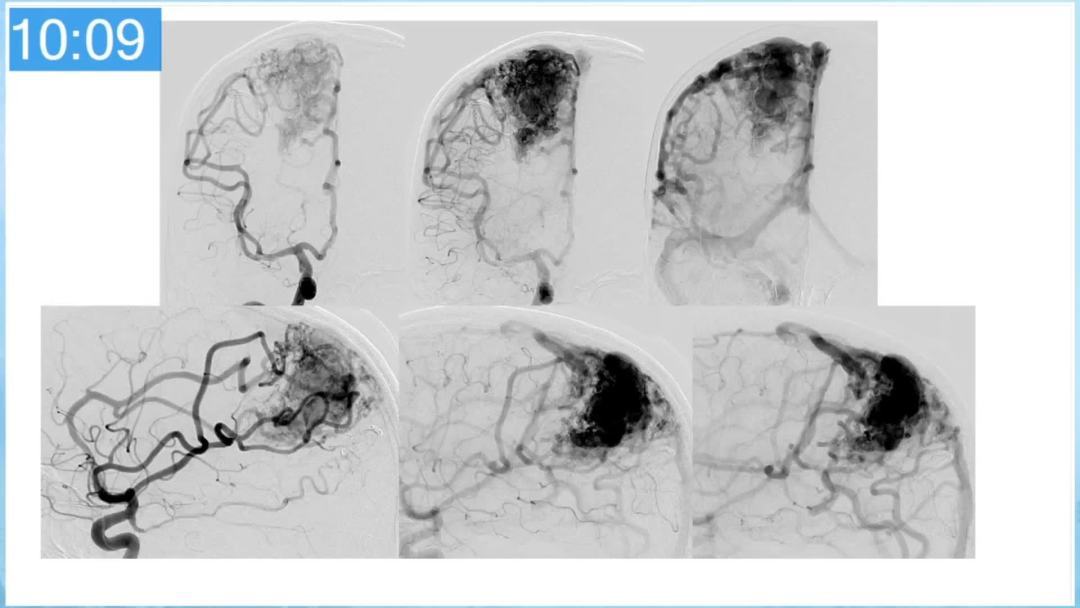

本期为大家特别分享:空军军医大学唐都医院邓剑平教授的精彩会议内容《颅内动静脉畸形的复合手术治疗》,欢迎大家阅读和分享!